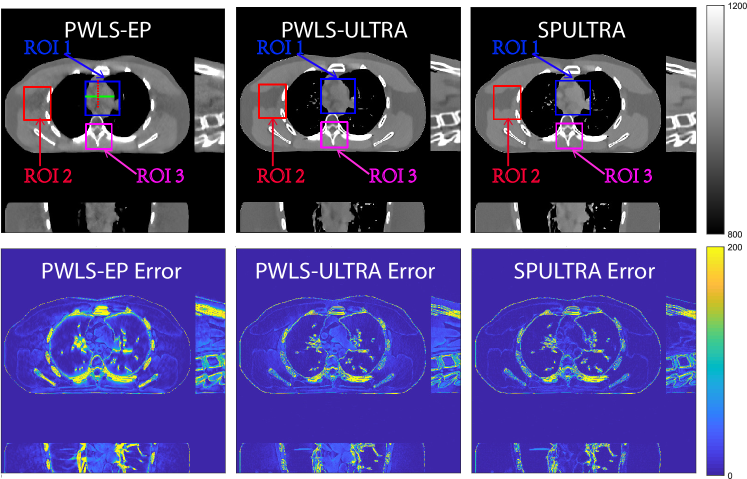

Fig. 4 shows the reconstructed images and the corresponding error images for PWLS-EP, PWLS-ULTRA, and SPULTRA, at and . Compared to the PWLS-EP result, both PWLS-ULTRA and SPULTRA achieved significant improvements in image quality in terms of sharper reconstructions of anatomical structures such as bones and soft tissues, and suppressing the noise. However, the PWLS-ULTRA method introduces bias in the reconstructions, which leads to larger reconstruction errors compared to the proposed SPULTRA method. In Fig. 4, we marked three 3D ROIs in the axial plane, i.e., ROI 1, ROI 2, and ROI 3. Fig. 5 shows the zoom-in images of a 3D plot of ROI 1, and those of ROI 2 and ROI 3 are shown in the supplement. We also plot the evolution of RMSE through the axial slices of the three 3D ROIs in Fig. 6. The figures demonstrate that SPULTRA clearly outperforms the competing PWLS-EP and PWLS-ULTRA schemes.

The above advantages of SPULTRA can be seen more clearly when observing the image profiles. Fig. 7 plots the image profiles for the three methods together with that of the ground-truth image. Fig. 4 shows the horizontal green solid line and the vertical red dashed line, whose intensities are plotted in Fig. 7. It is obvious that the profiles for SPULTRA are closest to the ground-truth among the three compared methods. The gap between the profiles of the PWLS-based methods and the ground-truth shows the bias caused by the compared PWLS methods.